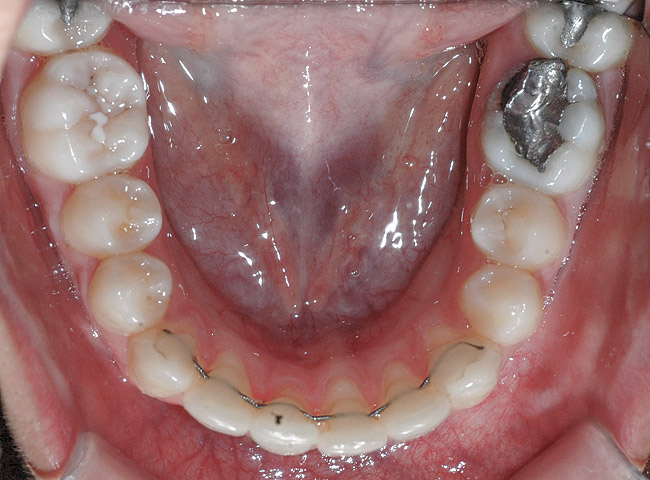

Fig 16. Occlusal view of patient shows the difference in angulation between the affected and the adjacent incisors.

Figure 16

Fig 20. Occlusal view after second orthodontic treatment showing corrected B-L inclination.

Figure 20